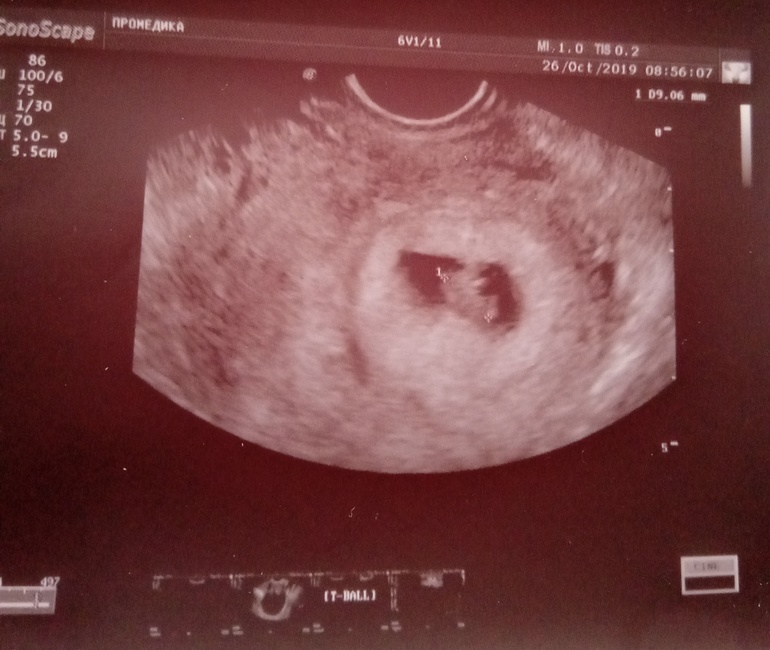

Ну что ж , сходила я на УЗИ.

Срок по кд 8 , по УЗИ 8

Ктр13 мм, чс 152

Ну и наша креветка 😊